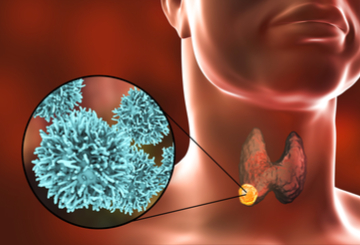

非常高兴地宣布并邀请您参加第十二届国际 DIP 暨展览会FemTech 创新围产期医学研讨会:改善全球孕产妇后代健康于 2024 年 5 月 23-25 日举行意大利索伦托,自第一次第一次 会议以来,DIP 研讨会取得了巨大发展,涵盖了 80 多年的知识、创新研究和最新进展-最新的工具、技术和综合方法。DIP 是母婴医学领域的领先研讨会,提供数据和管理方案,以确保合并糖尿病、高血压和代谢综合征的妊娠获得最佳结果。

与之前的会议一样,第 12 届 FemDIP 研讨会将重点介绍怀孕的进展:从怀孕前、三个月到临产、分娩和产后护理,还将创建一座连接医疗/科学和女性科技社区的桥梁。研讨会的初创企业馆 将为初创企业提供与行业关键人物交流的机会。重点关注妊娠并发症(高血糖、高血压、先兆子痫、早产、非传染性疾病)和妊娠、胎儿生长等的预测和预防,以及未来非传染性疾病的周期这始于子宫内的生活——影响到母亲和后代。我们将扩展到不断发展的女性科技领域,这将丰富科学项目,增加初创企业和投资者之间的交流机会,当然,还会鼓励分享知识以改善生活质量,为那些最需要帮助的人。

研讨会由来自世界各地的知名专业人士和从业人员、孕产妇、胎儿和新生儿医学、基础科学、营养学、助产学、糖尿病、护士教育工作者等领域的领导者组成,研讨会将展示最新的临床和实验室知识革命,基于证据和实践经验。